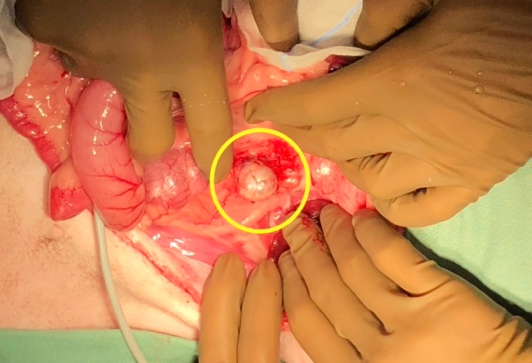

脾臓腫瘍

腫瘍が大きくなることでお腹の腫れなどを認めることがあります。また腫瘍が破裂することにより、腫瘍からの出血量によっては急性の虚脱や劇的な症状を伴うこともあります。

犬では血管肉腫が最も多い腫瘍であり、ジャーマンシェパードやレトリーバー種で発生が多いと言われています。

猫では脾臓の腫瘍は犬ほど多くはないが、猫では脾臓疾患の15%を肥満細胞腫という腫瘍が占めます。